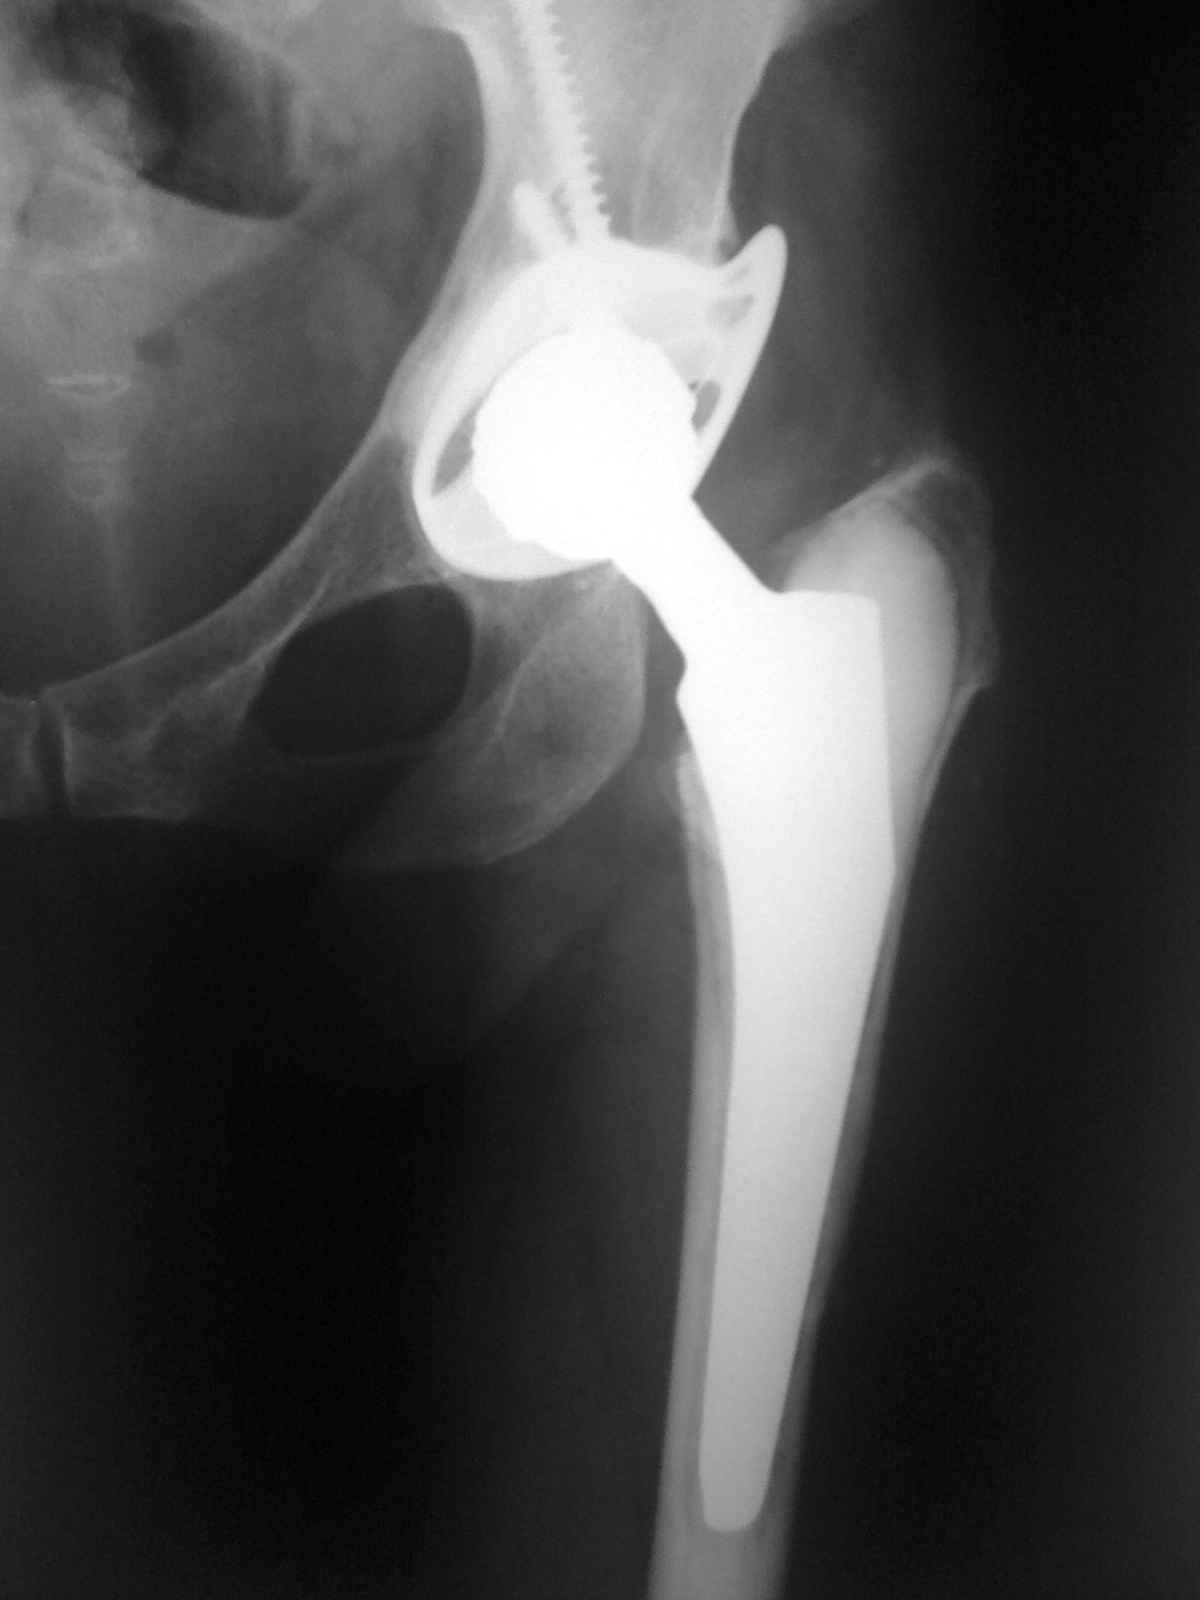

12 лет назад пациентке по поводу ревматоидного полиартрита выполнено ТПТС. Проблем не было.

7 дней назад в покое без видимых причин возникла резкая боль в паховой области. Боль постепенно усиливалась и к вчерашнему вечеру стала нетерпимой. Обратилась к хирургами по месту жительства. Заподозрено ущемление бедренной грыжи. Взята в эстренном порядке в операционную. На операции выявлена напряженная гематома со сгустками идущая из области вертлужной впадины. источник кровотечения не выявлен. Гематома эвакуирована, задренирована. Вопрос. Причина? Тактика дальнейшего ведения?